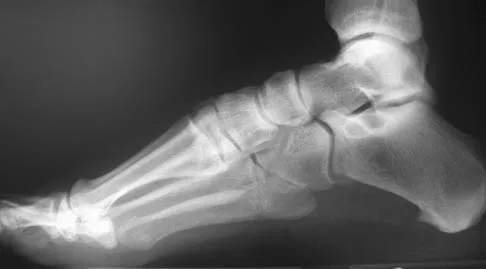

A patient with rheumatoid arthritis with both ankle and subtalar involvement was treated as shown in Figures 11a and 11b. What complication is unique to this type of fixation?

Explanation

The interlocking screws at the proximal end of the rod can act as a stress riser and lead to fracture. Postoperative pain at this level should prompt inclusion of this diagnosis in the differential. Removing the screws following bone union can decrease the chances of this occurring. A short rod that avoids the diaphyseal area may also be beneficial. Rotatory deformity is controlled by the perpendicularly oriented distal transfixion screws. Talar osteonecrosis would be unusual since the dissection can be minimized with an intramedullary rod. Any type of hardware can fail if the construct does not lead to a solid arthrodesis. Nunley JA, Pfeffer GB, Sanders RW, et al (eds): Advanced Reconstruction: Foot and Ankle. Rosemont, IL, American Academy of Orthopaedic Surgeons, 2004, pp 236-237. Thordarson DB, Chang D: Stress fractures and tibial cortical hypertrophy after tibiotalocalcaneal arthrodesis with an intramedullary nail. Foot Ankle Int 1999;20:497-500.